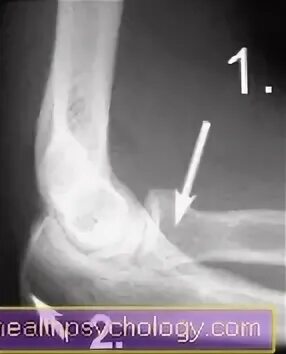

Перелом локтевого отростка рентген. перелом головки лучевой кости рентген. перелом локтевой кости рентген. перелом головки лучевой кости локтевого сустава со смещением.

Перелом локтевого отростка рентген. перелом шейки лучевой кости рентген локтевого сустава. перелом венечного отростка рентген. внутрисуставной перелом локтевой кости.

Синовиома локтевого сустава рентген. перелом локтевого отростка рентген. рентгенография локтевого сустава у детей норма.